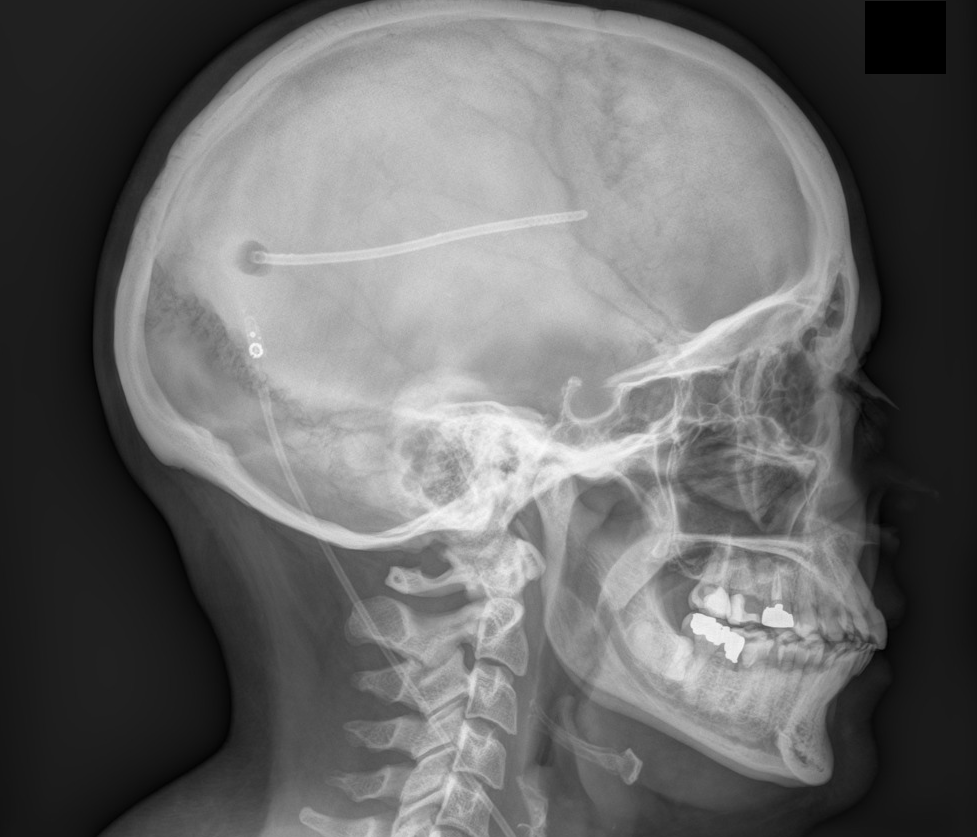

Η χειρουργική επέμβαση έχει σαν στόχο την διοχέτευση του (πλεονάζοντος) υγρού από τις κοιλίες του εγκεφάλου προς ένα άλλο μέρος του σώματος, όπου γίνεται απορρόφησή του. Το μέρος αυτό είναι συνήθως η κοιλιά. Το σύστημα που τοποθετείται ονομάζεται βαλβίδα παροχέτευσης (ventriculo-peritoneal shunt ή V-P shunt).

Αποτελείται από τρία μέρη :

1. από το κεντρικό σωληνάκι (καθετήρα) που απομακρύνει το υγρό από τον εγκέφαλο

2. από την βαλβίδα καθαυτή, που ρυθμίζει τη ροή του υγρού, δηλαδή πόσο υγρό θα παροχετεύεται

3. από το περιφερικό σωληνάκι (καθετήρα) που διοχετεύει το υγρό στην κοιλιά του ασθενούς.

• μετά τη χορήγηση γενικής αναισθησίας, γίνεται τομή στο δέρμα του κεφαλιού, πίσω και πάνω από το αυτί και ανοίγεται μία κρανιοανάτρηση (τρύπα) στο κρανίο διαμέτρου περίπου 2 εκατοστών, μέσω της οποίας εισάγεται το κεντρικό σωληνάκι (καθετήρας)

• επίσης, ανοίγεται δεύτερη τομή, στην περιοχή της κοιλιάς

• μετά τοποθετείται υποδορίως (δηλ. κάτω από το δέρμα) το περιφερικό σωληνάκι μέχρι την περιοχή της κοιλιάς

• γίνεται σύνδεση των τριών μερών, δηλ. της βαλβίδας με τα δύο σωληνάκια

• τέλος ελέγχεται η βατότητα του συστήματος (δηλ. επιβεβαιώνεται ότι το υγρό τρέχει ελεύθερα) και το περιφερικό σωληνάκι τοποθετείται μέσα στην κοιλιά. Ακολουθεί η συρραφή των δύο χειρουργικών τραυμάτων.